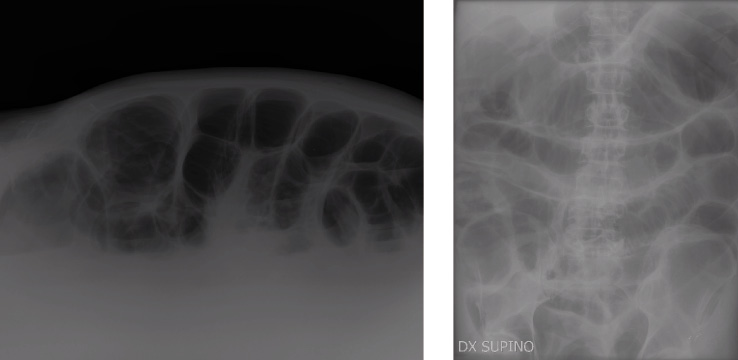

Si provvede, pertanto, a incrementare la reidratazione endovenosa, a ripetere gli esami emato-chimici e quelli colturali con ricerca delle tossine A e B del Clostridium difficile nelle feci. Nelle ore successive si ha, però, un peggioramento delle condizioni generali e, in attesa dell’Rx addome di controllo (Figura 3) e di una rivalutazione chirurgica, si apprende telefonicamente dal Laboratorio di Microbiologia la positività per antigene e tossine A e B del Clostridium difficile. Pertanto viene prontamente sospesa la terapia con tazobactam-piperacillina e prescritta vancomicina per os 500 mg per 4/die lasciando invariata la posologia di metronidazolo.

Figura 3. Rx addome di controllo che, confrontato con la precedente indagine, presenta incremento della distensione meteorica delle anse del tenue, con presenza di multipli livelli idroaerei nel radiogramma eseguito in proiezione tangenziale. Non aria libera